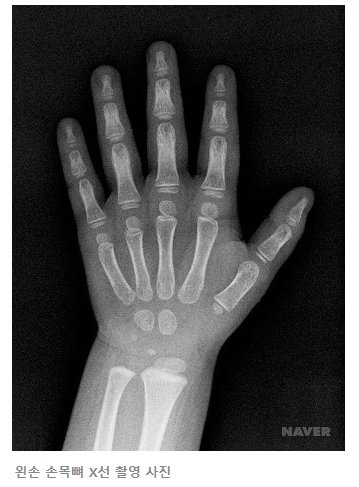

뼈나이(Bone age)는 한 마디로 검사 대상자의 골 성숙 정도를 나타내는 나이입니다. 뼈나이(골연령)의 평가 방법은 다양하나 X-ray 촬영을 이용한 뼈나이 평가가 가장 많이 사용됩니다. 일반적으로 뼈나이는 왼손을 X-ray로 촬영한 뒤 척골, 요골, 수근골, 중수골, 수지골 등의 골 성숙도를 비교하여 그로일리히-파일(Greulich-Pyle) 방법 또는 태너-화이트하우스(Tanner-Whitehouse) 방법에 의하여 평가합니다.

| * 뼈나이(골연령)의 평가방법(참고) 1. 그로일리히-파일(Greulich-Pyle) 방법 그로일리히와 피일 방법은 도보식 평가법으로 도보(각 연월령을 대표하는 X선 사진)에 나타난 표준 방사선 사진과 비교하여, 골 성숙도가 가장 근접한 표준 연령을 찾아 골연령으로 읽는 것이다. 2. 태너-화이트하우스(Tanner-Whitehouse) 방법 972년 태너-화이트하우스에 의해서 추적 검사와 횡단면 검사로 만들어졌다. 왼손과 손목의 7개의 수근골, 11개의 수지골, 요골과 척골의 원위부의 총 20개의 골을 각 모양과 밀도를 분석하여 A부터 H 또는 I까지, 8단계 또는 9단계로 나누어 분석한다. |